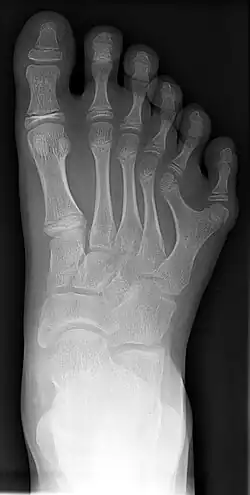

Radiografia de um com polidactilia (pododáctilos).

A polidactilia ou polidatilia (do grego πολύς, "muitos" e δάκτυλος "dedo") é uma anomalia causada pela manifestação de um alelo autossômico variável,dominante com expressividade consistindo na alteração quantitativa anormal dos dedos da mão (quirodáctilos) ou dos dedos do (pododáctilos).

Há uma variação muito grande na expressão dessa característica, desde a presença de um dedo extra, completamente desenvolvido, até a de uma simples profusão carnosa.